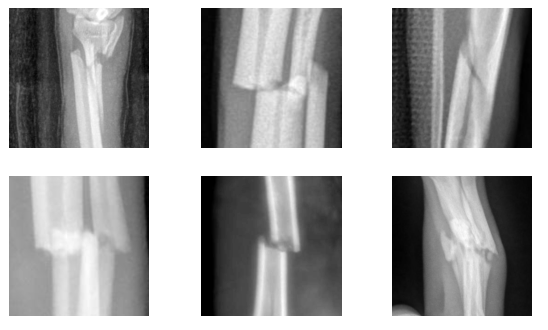

We ultimately select six clusters. This choice aligns with the major visual features we wish the model to recognize, achieving a balance between optimization and interpretability. Figure 2 showcases a representative sampling of images belonging to each cluster. This categorization helps in understanding the nature of the classifier’s outputs and enriches insights into whether the clusters are being formed based on features that are both interpretable and logically coherent.